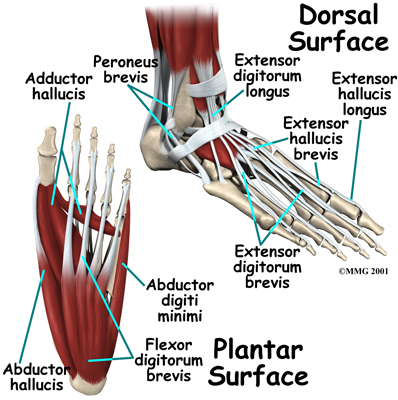

The strong muscles and tendons in the lower leg that connect directly to the foot create most of the motion of the foot. Contraction of these muscles is the main way that we move our feet to stand, walk, run, and jump.

The strong muscles and tendons in the lower leg that connect directly to the foot create most of the motion of the foot. Contraction of these muscles is the main way that we move our feet to stand, walk, run, and jump.

There are numerous small muscles in the foot. While these muscles are not nearly as important as the similar small muscles in the hand, they do affect the way that the toes work. Most of the muscles of the foot are arranged in layers on the sole of the foot (the plantar surface). There they connect to and move the toes as well as provide padding underneath the sole of the foot. Damage to these muscles can cause problems in the foot.